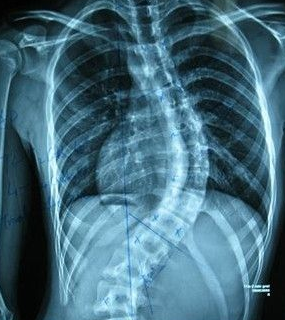

强直性脊柱炎治疗